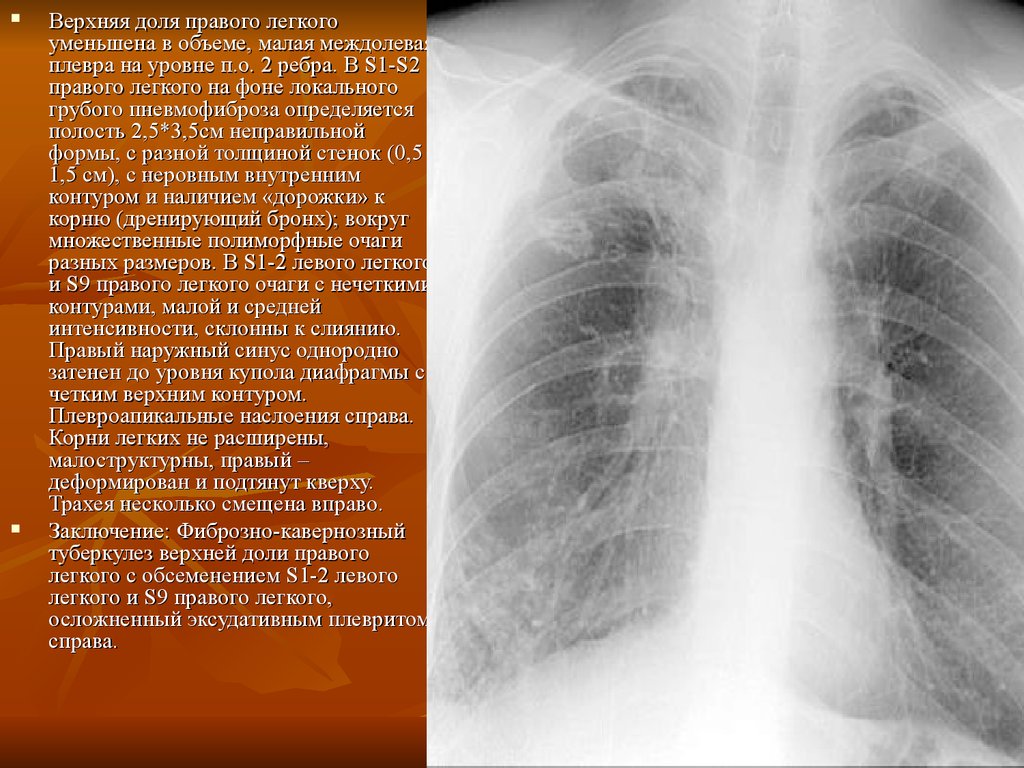

Роль легких в метаболических процессах